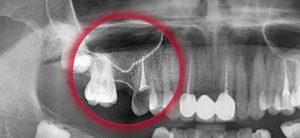

На фото видна перфорация дна гайморовой пазухи после удаления зуба

- Рентгенография области пазух. На снимках в таком случае можно обнаружить как затемнение полости вследствие скопления в ней крови, так и обломки зубных корней, импланты либо пломбировочный материал. Иногда целесообразно проведение рентгенографии с конрастированием, когда контрастное вещество вводится в полость через перфорационный свищ.

Далее необходимо определить, попало ли инородное тело в полость синуса. Делать это нужно немедленно с помощью компьютерной томограммы или серии рентгеновских снимков, которые выявят степень сложности перфорации.